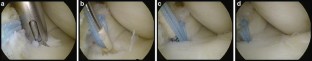

Fig. 2